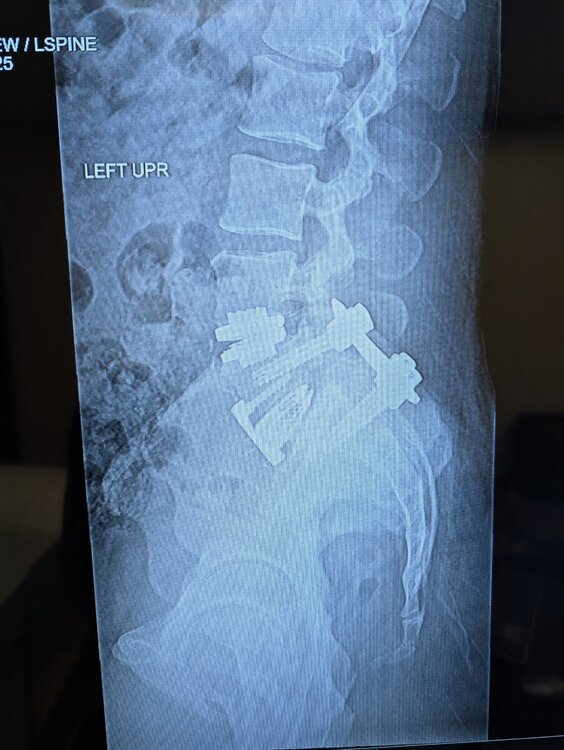

I got a spinal fusion and disc replacement two weeks ago and looks like everything has set well. I lifted and moved the last 20 years so not being able to bend, twist, or lift over 10 lbs until July sure will be a mental challenge.